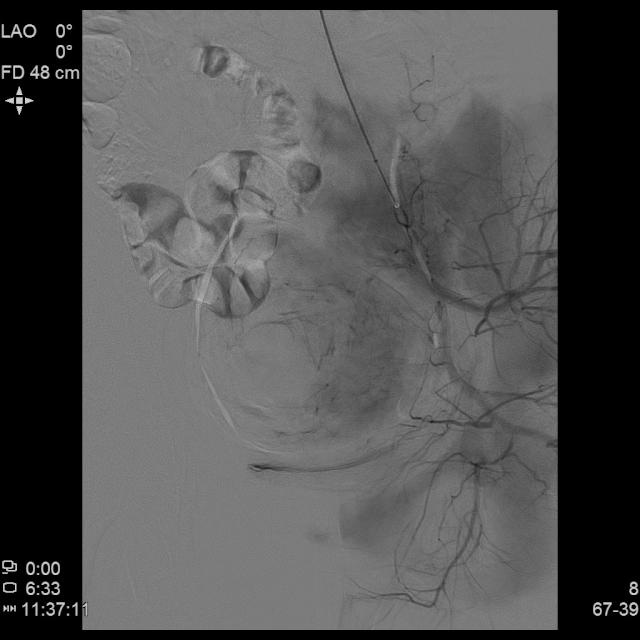

- 进一步超选插管左侧子宫动脉造影确认位置